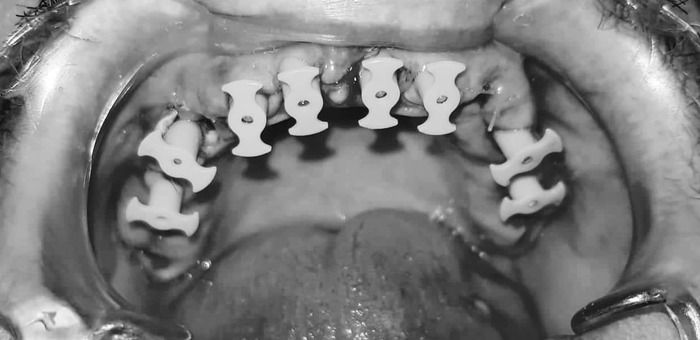

Теперь - как это все дело выглядело в реале:

Вот честно, пока я не увидел именно эти две фотки - я слабо осознавал, какой именно у меня пипец во рту. Каждое утро в зеркале это воспринималось немного не так. Передергивало, конечно, но было привычно. Кстати, все эти фото я увидел уже сильно после лечения и никакого влияния на мое решение лечиться у Георгия они не оказали - не успели )))

А дальше, 3 ноября, за 3 часа времени со мной сделали вот это:

Заметили на последней фотке, какие у меня нижние зубы?